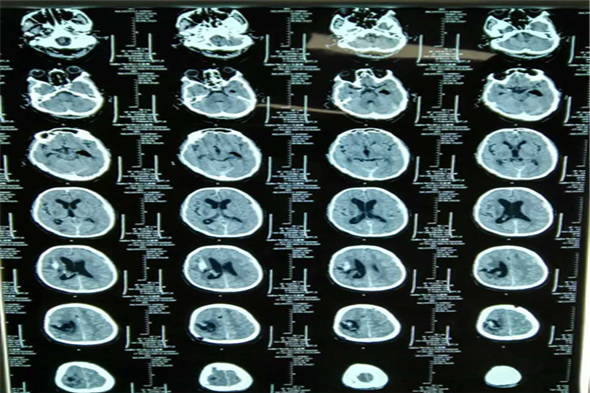

神经外二科近期收治3名大量脑出血的病人,其中2名患者已经出现了脑疝,生命垂危,入院后吴卫东主任果断决定行急诊微创手术治疗,行一侧钻孔血肿清除引流术加一侧脑术外引流术。术后病人恢复较好,一侧散大瞳孔回复,生命体征平稳,现已进入康复治疗阶段。以下为3名患者术前术后CT检查结果。

病例三 王某,男,66岁,脑出血、脑疝。

术前脑CT片

术后第三天脑CT

术后一周脑CT